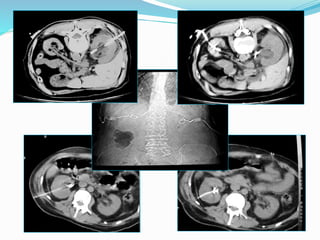

ΝΕΦΡΟΣΤΟΜΙΕΣ

Ενδείξεις

.Απόφραξη του αποχετευτικού συστήματος

εξαιτίας εσωτερικής ή εξωτερικής απόφραξης του

ουρητήρα λόγω:

.Λίθων

.Κακοήθειας

.Ιατρογενώς

.Πυονέφρωση ή επιμολυσμένη υδρονέφρωση:

.Gram (-)

.Ιατρικό επείγον